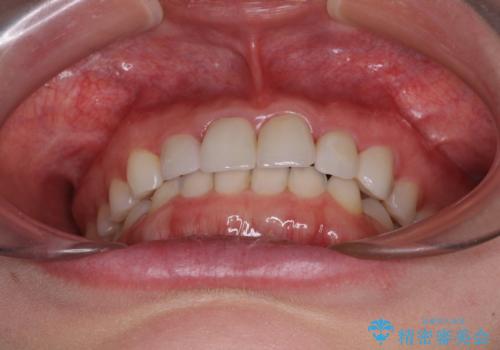

上下前歯の歯列不正はインビザラインにより歯列を整え、その後に、前歯5本をオールセラミッククラウンにて補綴治療することとしました。

矯正治療にて歯並びを整えた後に、虫歯の大きかった5本の歯をセラミッククラウンにて補綴し、明るい口元になりました。